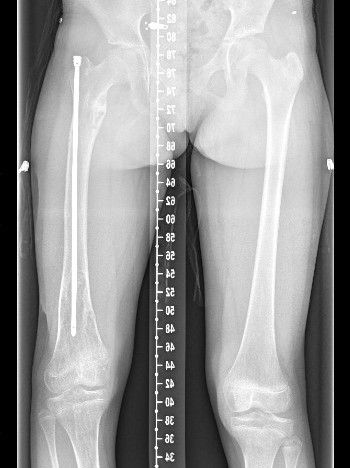

Leg length discrepancy

Popkov et al Orthop Traumatol Surg Res 2010

- limb lengthening in Olliers

- external fixator versus external fixator + IM nail

- use of nail reduced external fixator time, complications, and fractures